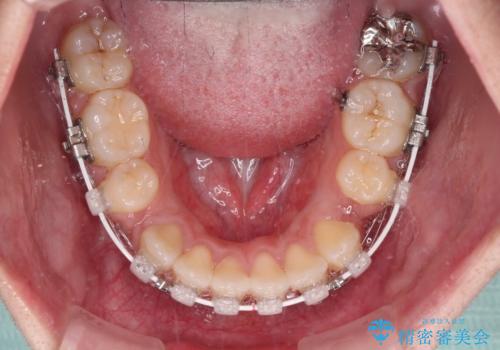

- 口元の突出感を気にして来院された患者様です。

デコボコと口元の突出感が認められたため、上下左右の第1小臼歯4本を抜歯してのワイヤー矯正を行うこととしました。

上顎歯列の横幅が狭く、下顎大臼歯の歯軸が舌側に倒れていたため、急速拡大装置により上顎骨を側方に拡大し、咬み合わせを改善することとしました。

上顎歯列幅を拡大したことで、デコボコを容易に解消することができるようになったため、抜歯により得られたスペースを口元の突出感改善に利用することができました。